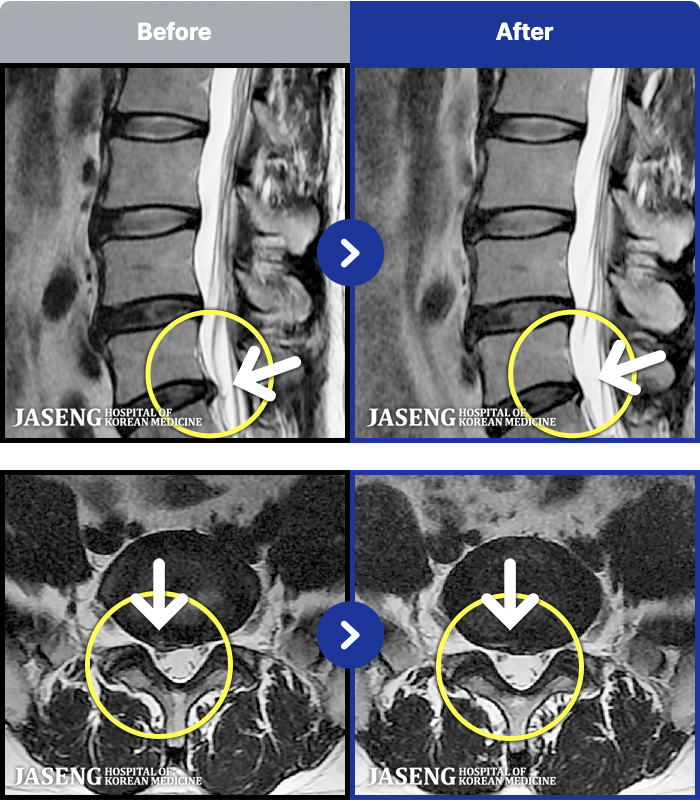

[뱸] 19.11.28~25.05.06